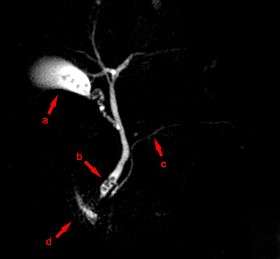

![]() MRCP image showing stones in the distal common bile duct: (a) Gallbladder with stones, (b) Stones in bile duct, (c) Pancreatic duct, (d) Duodenum. | |

Magnetic resonance cholangiopancreatography (MRCP) is a medical imaging technique that uses magnetic resonance imaging to visualize the biliary and pancreatic ducts in a non-invasive manner.[1] This procedure can be used to determine if gallstones are lodged in any of the ducts surrounding the gallbladder.